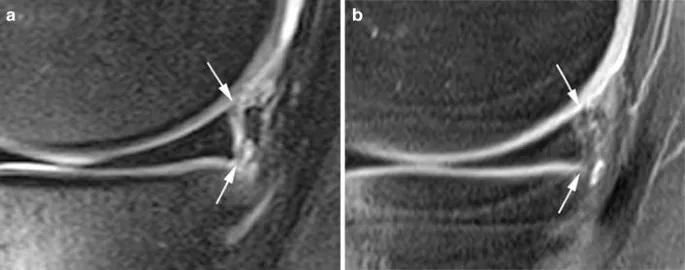

- MSK - Knee:

- Menisci (medial C-shaped, lateral O-shaped): Normal low signal. Tears: ↑ signal reaching articular surface.

- Ligaments: ACL, PCL, MCL, LCL - assess integrity, tears (↑ signal, discontinuity).

⭐ Fluid-sensitive sequences like T2-weighted with fat suppression (T2 FS) or STIR are crucial in MSK MRI for detecting edema, inflammation, and fluid in ligamentous/meniscal tears.